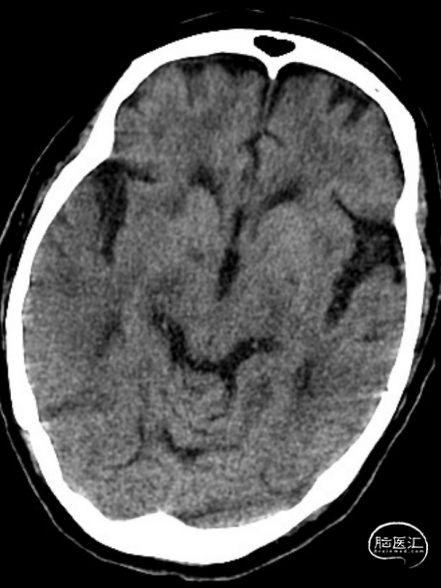

术后第一天复查颅脑CT未见异常染色及大面低密度病灶。

查头颅MRI:右侧基底节区、右侧顶颞岛叶急性脑梗死。